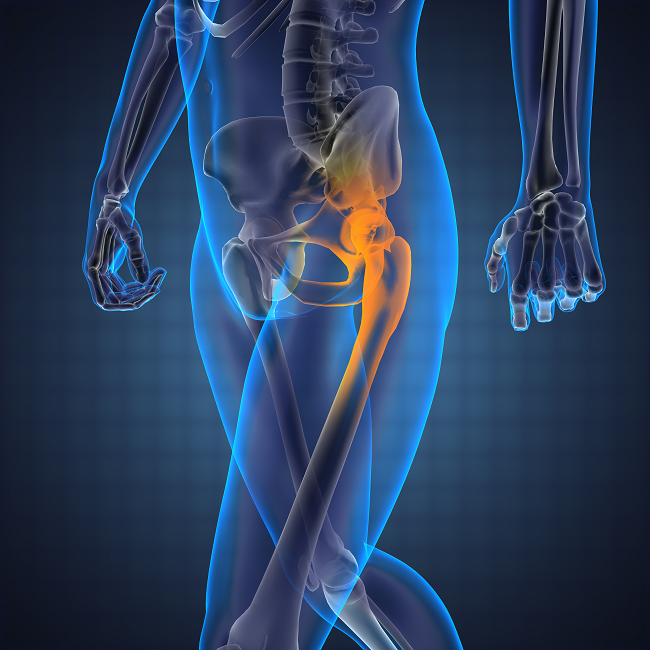

Arthroplasty means joint reconstruction. When a joint is damaged and causes problems for the patient, the damage may be so great that surgery is needed.

In this situation, different surgeries may be used, one of which is joint replacement. In joint replacement surgery, part or parts of the joint are replaced with an artificial component.

For example, this type of surgery may be needed when the hip joint is severely damaged. So joint replacement is a type of arthroplasty.

Your doctor may decide to just remove the femoral head from the body and replace it with a prosthetic metal head. Because only half of the joint has been changed in this condition, this procedure is called hemi arthroplasty .Sometimes orthopedists have to replace both the femoral head and the acetabular cavity (Complete hip replacement); This type of surgery is called total arthroplasty. Therefore, total hip arthroplasty is a type of orthopedic surgery in which the hip joint is Completely replaced with an artificial joint.